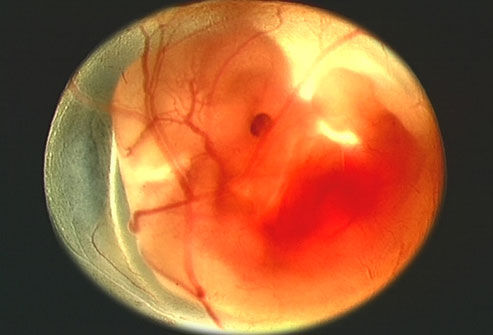

一个月:每一个月新生命的成长比任何时期都快,要比受精卵长大一万倍。动脉、静脉已形成,且有血液流动;脑、肾、消化管已见雏形;脐带已开始工作;心脏形成且开始跳动。

两个月:胚胎外形已初步具备了人的模样。头占全身的一半,胚胎颜面已显现出来,有舌及尚未成熟的牙床,臂上 已有手指,腿上有了膝盖、足踝和脚趾,胚胎全身覆盖着一层薄薄的皮肤;大脑和性器官都开始发育,心脏跳动稳定,胃开始分泌消化液,肝脏开始制造血细胞;肾 脏已开始工作,可排出血中的尿液;皮肤敏感性增强,对触觉刺激可做出反应。